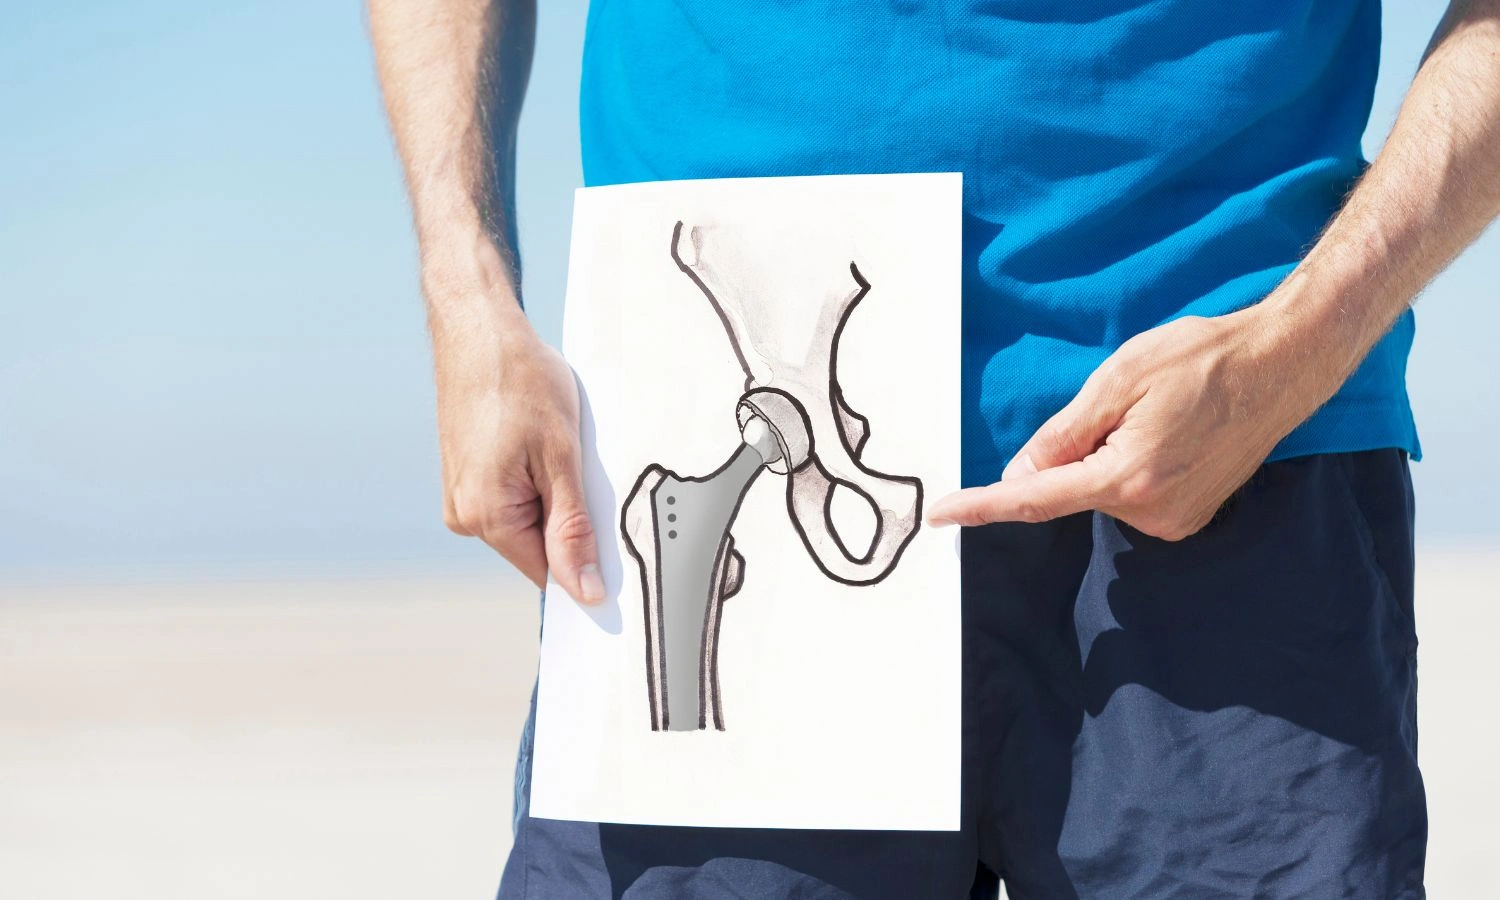

Hip Replacement

Hip replacement surgery, also known as hip arthroplasty, is a common procedure performed to relieve pain.